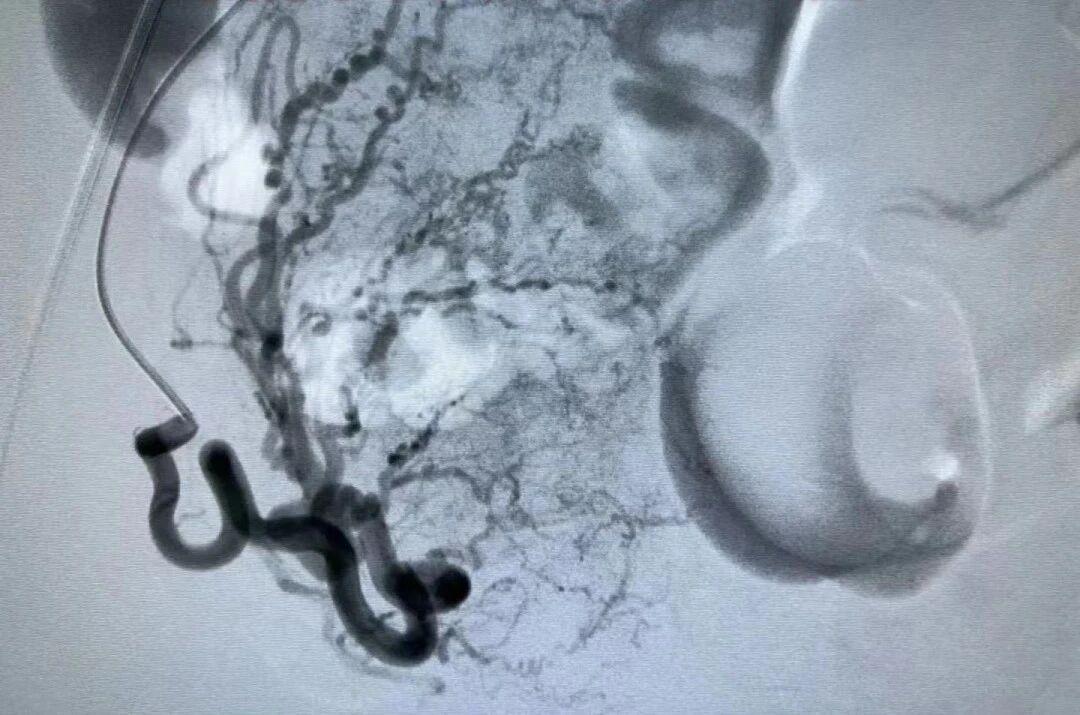

具体来说,这种治疗方法是通过子宫动脉造影,经右股动脉刺入导管,直接注入栓塞微球堵塞异位子宫内膜的供血血管,直接切断子宫腺肌症异位的子宫内膜血液供应,使腺肌症病灶被“活活饿死”。

子宫动脉栓塞术是目前保留子宫、治疗子宫腺肌症的有效手段之一,能很好地保留腺肌病子宫器官和功能的完整性。